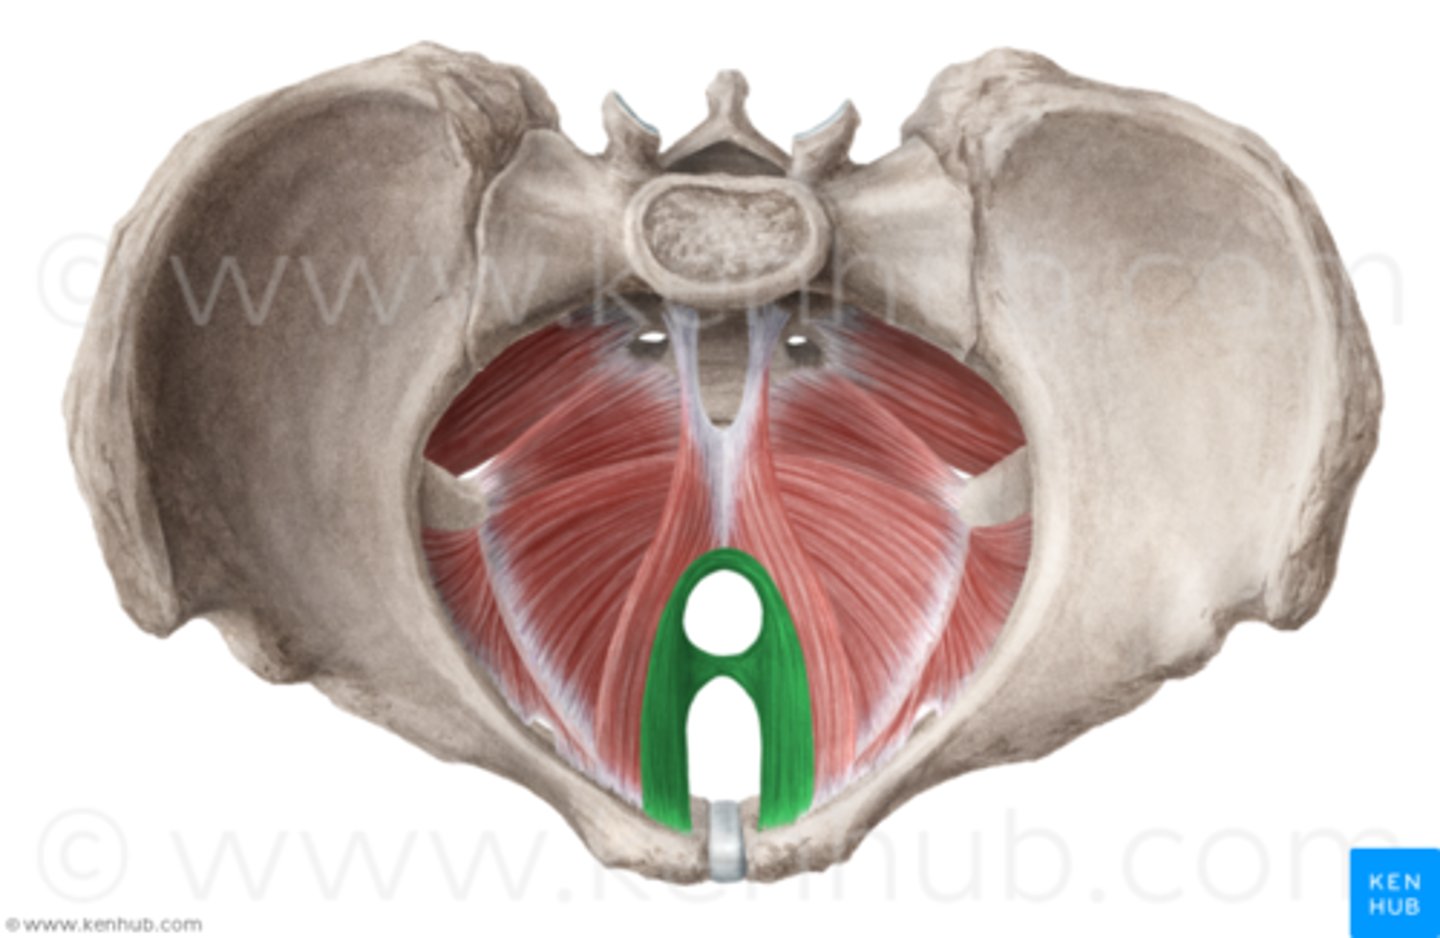

Puborectalis

O: anteriorly, from pubic symphysis

I: posteriorly, around anorectal junction

A: inhibits and also aids in defecation, and flatulence

What is the result of damage to puborectalis?

involuntary farting and defecation

pelvic floor injury

-extremely common consequence of vaginal delivery

-puborectalis and pubococcygeus are most common muscles damaged, causing incontinence and sexual dysfunction